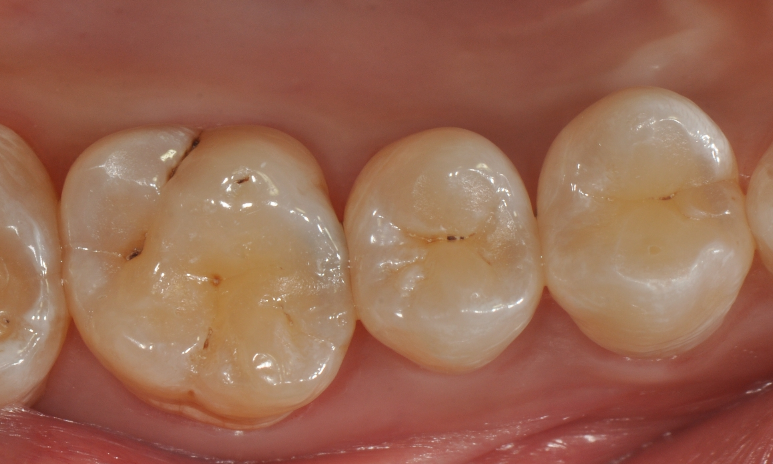

牙医-马小寒【实操病例】

右上6号牙位的近中,可见隐约龋坏

◆去腐完成之后